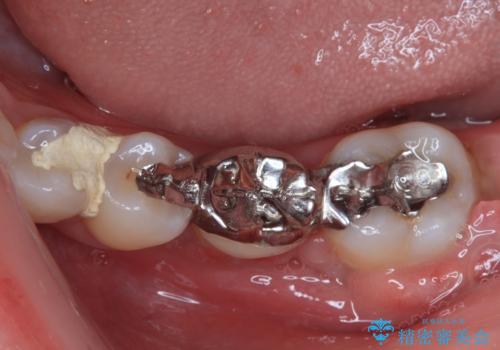

- ブリッジの歯のないところにインプラントを入れて、銀歯を白くやり替えたいと来院された患者様です。

歯の欠損している箇所にはインプラント治療をし、銀歯と仮詰めの部分はセラミックインレーにて補綴することとしました。